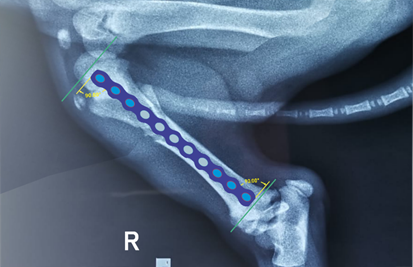

Se resolvió sin complicación intraoperatoria, en las radiografías posoperatorias inmediatas se observaron el implante en su posición (Figura 5 y 6), se recomendó realizar placas de rayos X de control a 20 y 40 días después de la cirugía hasta evidenciar radiográficamente la unión ósea, por otro lado, se indicó a los propietarios sobre caminatas reducidas y un espacio regular durante las primeras 2 semanas de intervención quirúrgica. El tratamiento antibiótico, antinflamatorio posoperatorio de administración Ketoprofeno (2 mg/kg iv, c/24 h), Tramadol por vía oral (2 mg/kg c/8 h) para manejo del dolor, Cefalexina (20 mg/kg im, c/12 h) para evitar infecciones secundarias por 3 días.

Figura 5 alineaciones en el plano sagital en la proyección mediolateral, placa bloqueada de holes de 9 mm y tornillos de bloqueo de 3.2 mmx12 mm, 8 mm

En nuestro caso se observó esta limitación a pesar de ser una técnica OPMI existe un espacio de 3 mm aproximadamente detalle que se muestra en la (Figura 5) mediciones de aproximación entre los segmentos de fractura que se pudo obtener con las placas radiográficas de tamaño real.